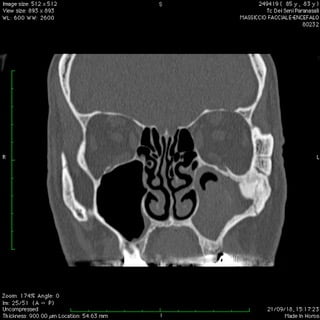

Anche nelle sinusiti la peculiare morfologia anatomica delle strutture coinvolte, cavità ossee, consente nella maggior parte dei casi latenze di esordio molto ritardate rispetto il primitivo insorgere patologico palesandosi così in avanzate fasi di compromissione .

Nelle forme croniche, cioè di malattia stabile nel tempo, i seni paranasali diventano “ siti di decantazione”, ovvero di ristagno e moltiplicazione,per germi di vario genere dando vita così ad un persistente primario serbatoio contaminante sia le vie aeree che quelle digestive.